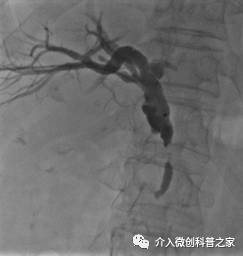

中晚期腺癌内部放射性粒子近距离照射治疗

(近距离照射杀死癌细胞、止痛效果好)